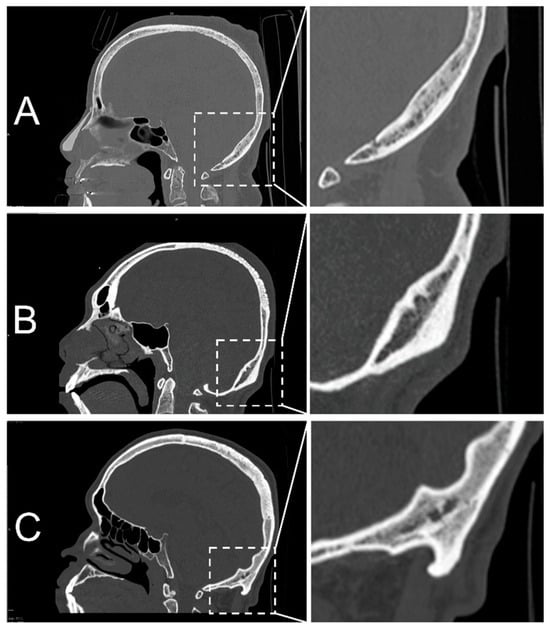

2.4. Classification of EOP Types

2.5. Morphometric Measurements